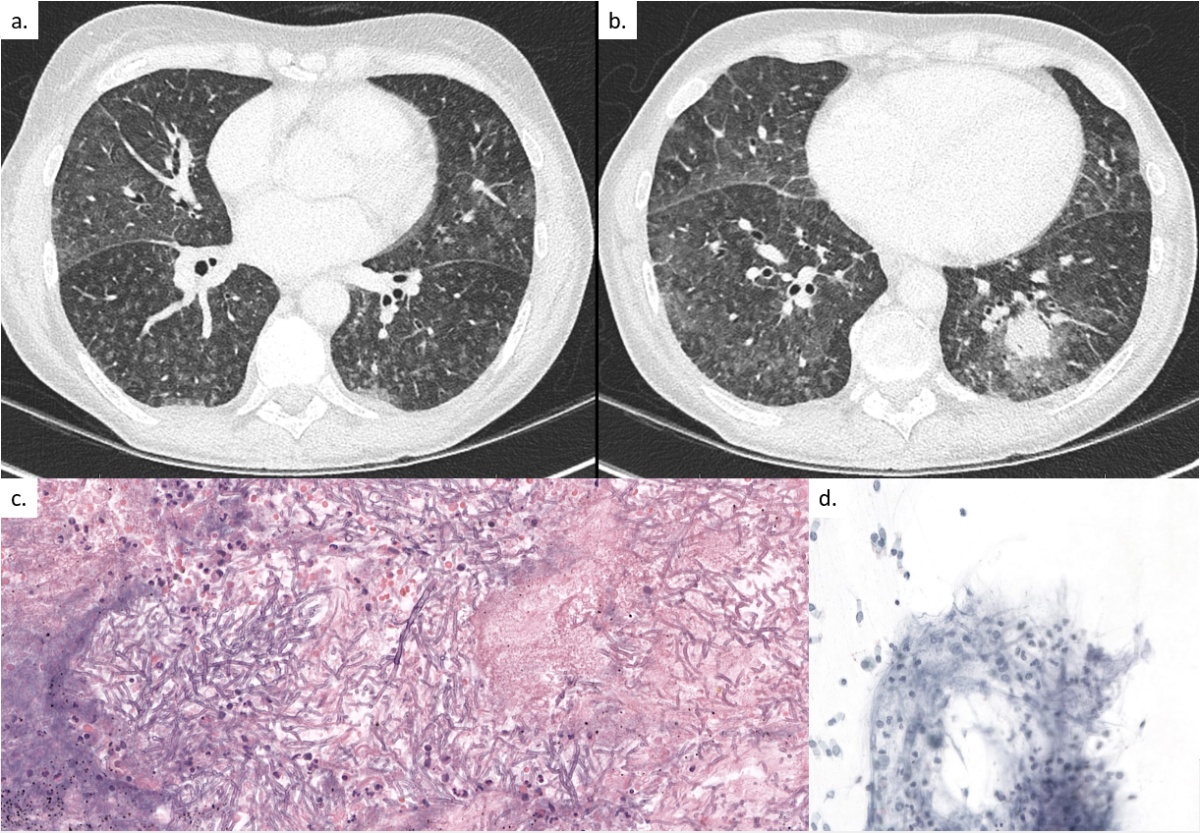

Figure 1 (a) Pulmonary computed tomography (CT) on day 12 showing diffuse ground-glass opacities with numerous micro-nodules, primarily in the superior lobes and the apical segments of the inferior lobes. (b) Pulmonary CT on day 23 showing progression of the diffuse bronchiolitis signs and a new nodular lesion of 2 cm in the left lower lobe with a halo sign. (c) Transbronchial biopsy on day 42 showing multiple, narrow, septated, branching hyphal forms on haematoxylin and eosin stain identified by PCR as Aureobasidium spp.. Abundant presence of lymphocytes, neutrophils, fibrocytes, bronchial cells and alveolar macrophages indicating an inflammatory process. (d) Part of the transbronchial biopsy on Grocott stain showing the fungal hyphal forms identified by PCR as Aureobasidium spp.

A 63-year-old patient, with a past medical history of large vessel vascultis treated with prednisone, was admitted for the first cycle of induction chemotherapy by idarubicin and cytarabine for myelodysplastic syndrome with excess of blasts type 2 (day 0). The prophylaxis regimen consisted of acyclovir 500 mg three times daily intravenously (IV), co-trimoxazole double-strength (DS) three times weekly orally (PO) and posaconazole 300 mg once daily PO. On day 9 the patient developed persistent neutropenic fever (day 9–15), treated with different broad-spectrum antibiotics, including cefepime, vancomycin, imipenem and levofloxacin. Thoraco-abdominal computed tomography (CT) on day 12 showed diffuse ground-glass opacities with numerous micro-nodules, primarily in the superior and the apical segments of the inferior lobes (fig. 1a). A bronchoscopy was performed on day 13 with a bronchoalveolar lavage (BAL) negative by bacterial and fungal stain, sterile culture, negative viral multiplex polymerase chain reaction (PCR) panel (adenovirus, human metapneumovirus, parainfluenza virus 1–4, rhinovirus, coronaviruses, SARS-CoV-2, influenza A/B, respiratory syncytial virus), Legionella spp. PCR and culture, Pneumocystis jirovecii PCR, Chlamydophila pneumoniae PCR, Mycoplasma pneumoniae PCR, Mycobacterium tuberculosis PCR, and broad-spectrum bacterial and panfungal PCR, and a specific Aspergillus fumigatus and Mucorales spp. PCR. Serum beta-D-glucan (Fungitell) and galactomannan enzyme immunoassay (Platelia Aspergillus Bio-Rad) were negative. Owing to a new episode of neutropenic fever on day 23, another chest CT scan was performed, which showed progression of the diffuse bronchiolitis and a new nodular lesion of 2 cm in the left lower lobe, prompting a second bronchoscopy on day 24 (fig. 1b). The repeat BAL was negative for all previously mentioned diagnostic tests. Because of persistence of neutropenic fever and a new appearing nodular lesion, posaconazole prophylaxis was discontinued and empirical antifungal therapy with liposomal amphotericin B at 5 mg/kg once daily IV was initiated on day 24. Neutropenia resolved by day 29 with rapid clinical improvement and, considering the negative results of both BALs, antifungal treatment was discontinued 10 days later (day 34) without reinitiating antifungal prophylaxis. On the same day, the patient developed a new non-neutropenic fever. A repeat chest CT was performed on day 41, showing the same left lower lobe nodular lesion, unchanged in size. After a seven-day “therapeutic window” with discontinuation of all antifungal treatment, a third bronchoscopy with a transbronchial biopsy was performed on day 42. All BAL stains, cultures and PCR tests (M tuberculosis PCR, Aspergillus spp. PCR, Pneumocystis jirovevii PCR, panfungal PCR, Mucorales spp. PCR) remained sterile and negative, respectively. The transbronchial biopsy was positive for multiple septate branching fungal hyphal forms (fig. 1c). A specific fungal stain (Grocott-Gomori) was positive (fig. 1d).